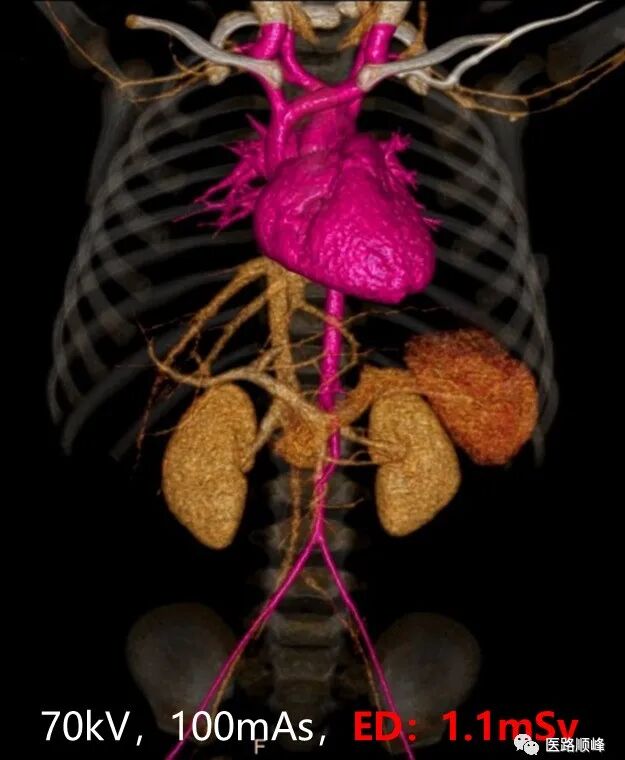

• 70kV低剂量检查

真正临床化的低剂量扫描,可应用于临床各部位检查,包括但不限于低剂量体检、低对比剂血管造影检查等。

ct为什么需要预热机器Computed Tomography专栏:Incisive CT 球管预热_https://www.jmylbn.com_新闻资讯_第20张